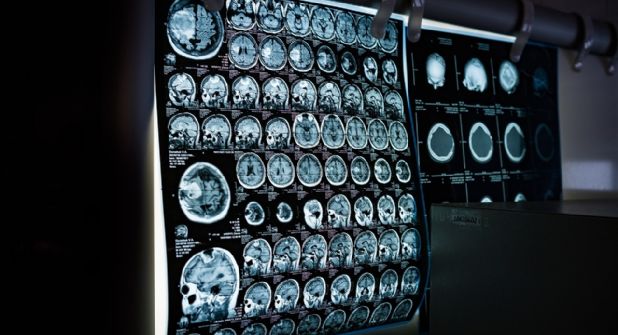

En primer lugar, se les practicaron resonancias magnéticas abdominales para evaluar la grasa localizada tanto bajo la piel como en los órganos internos. Además, se les realizó una evaluación metabólica que incluyó análisis de glucosa, colesterol y escáneres musculares de los muslos para medir el volumen de músculo y

Pero lo más importante fue el uso de la tomografía de emisión de positrones (PET), una técnica avanzada que permite observar la actividad y el metabolismo en el cerebro. Con esta herramienta, los investigadores pudieron valorar la presencia de Beta amiloide y Tau, las dos proteínas patológicas asociadas con el Alzheimer.